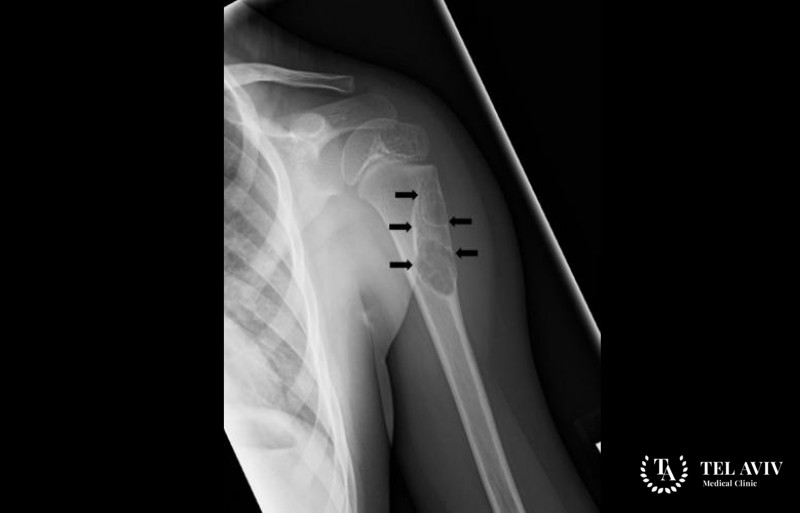

В медицине выделяют два типа костных кист. Солитарное образование – простой тип патологии. Легко диагностируется, поражает длинные кости. Чаще встречается у мужчин. Аневризмальные кисты – редкие патологии, поражающие детский, подростковый организм. Вместо жидкости полости наполняет кровь. Физическая травма может привести к формированию костного кистозного образования.

- Кисты в плечевых костных тканях вызывают боли, неприятные ощущения при поднятии рук, резком движении;